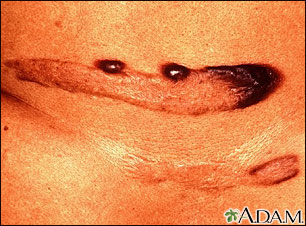

Los queloides son una proliferación del tejido cicatrizal que se puede desarrollar a partir de una herida e incluso de un trauma menor, como la perforación de las orejas. Los individuos de tez oscura tienden a formar queloides con mayor facilidad que los individuos de tez más clara. En este caso, las placas del queloide han adquirido una pigmentación intensamente oscura.